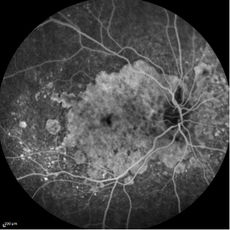

ESAME FONDO OCULARE: permette di valutare la papilla ottica e in particolare il rapporto tra la sua ampiezza e la sua escavazione (il cosiddetto rapporto CUP/DISC).

ESAME DEL CAMPO VISIVO: è l’esame indispensabile per effettuare diagnosi di glaucoma ed è molto utile nella fase di follow-up, per valutare la progressione del danno e l’efficacia terapeutica; l’esame del campo visivo computerizzato (o perimetria computerizzata) permette di determinare l’entità e la progressione del danno delle fibre nervose ganglionari.